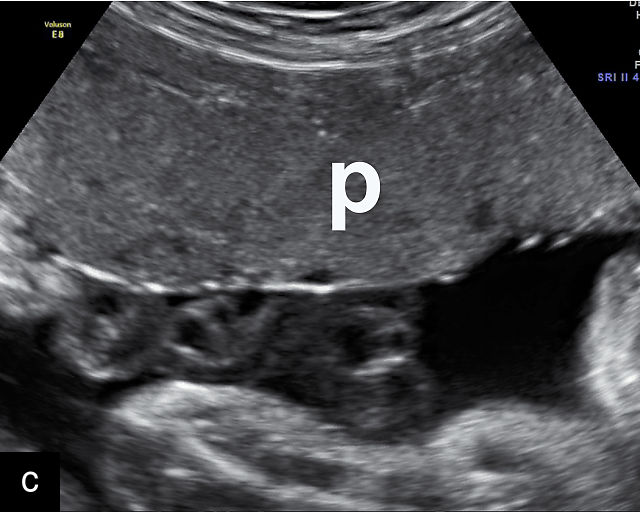

Placental lakes

Placental lakes are hypoechoic regions within the placenta and are the most common finding on ultrasound of the placenta (Figure 3; Video 1).2,9,13,16 They are surrounded by placental tissue of normal echogenicity.16 Some reports specify that hypoechoic areas should be at least 2 cm in size to qualify as lakes.13,17 On grayscale ultrasound, swirling of blood can be observed in lakes (Video 1). Low-velocity flow can be demonstrated using sensitive Doppler techniques. Lakes tend to be located in the center of placental cotyledons or under the chorionic plate (Figure 3).16 Other common locations are at the placental edge and between lobes in a bilobed placenta where they may be very large. Lakes tend to fluctuate in size over time. Several studies have found that placental lakes are not associated with an increase in adverse pregnancy outcome, regardless of size and number.13,18,19 However, one study found an increased risk of small-for-gestational age fetuses with larger placental lakes.20 Lakes must be differentiated from lacunae, which contain high-velocity blood flow and are associated with placenta accreta spectrum.16

3

(a–f) Placental lakes. Multiple hypoechoic spaces present in placenta (p), surrounded by placental tissue of normal echogenicity. Arrows in (e) and (f) indicate lakes.